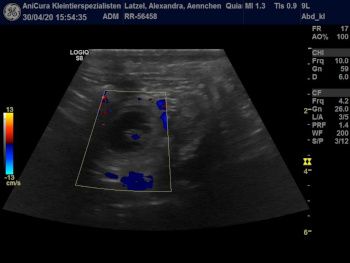

| Die Ultraschallbilder von Aennchen von Waltenweiler!!! |